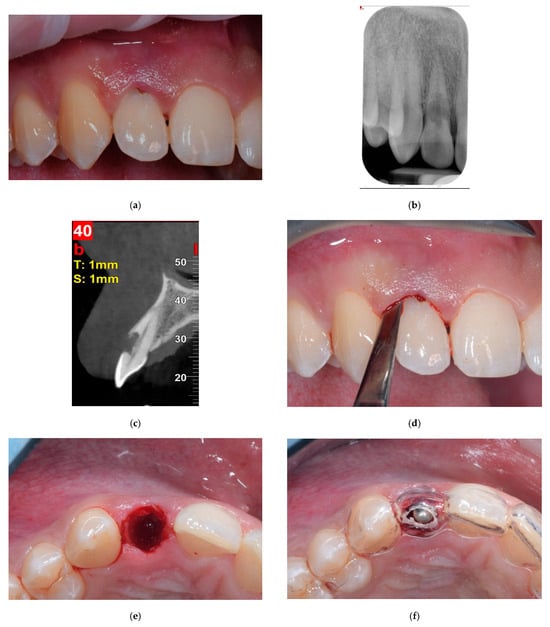

Figure 1.

Images from a case of immediate placement with immediate restoration. (a) Baseline situation showing an hopeless upper right lateral incisor with a root resorption. (b) Baseline intraoral x-ray showing the root resorption. (c) Baseline cone beam evaluation, the buccal bone plate is intact. (d) The tooth was extracted using dynamic-magnetic approach. (e) Due to a flapless minimally invasive approach, soft tissue profile was preserved. (f) Implant site preparation was conducted using a prosthetically guided surgical stent. (g) A conical edge implant 3.5 mm in diameter and 14 mm in length was inserted slightly palatal, leaving a bone-to-implant gap more than 2 mm pronounced on the buccal side, which was grafted with a bovine bone mineral. (h) Chairside, a provisional titanium abutment, was connected and luted to a provisional resin crown. (i) The provisional crown was connected to the implant and screwed. (j) Intraoral x-ray at the end of the surgery. (k) The definitive ceramic crown, three months after surgery. (l) Clinical image of the definitive ceramic crown in place, 12 months after implant placement. (m) Definitive radiological evaluation, 12 months from implant placement.

Before extraction, in order to provide a prosthetically driven implant positioning, slightly palatal for incisors/canines and centric to the occlusal plane for premolars, a surgical template was fabricated for each patient. The day of surgery, a minimally invasive flapless procedure was performed for tooth extraction. Maximum care was taken to minimize trauma to the socket walls when luxating and extracting the tooth by using a magneto-dynamic approach (Magnetic Mallet, Osseotouch, Gallarate, Italy) (Figure 1a–e). Following extraction, the socket was rinsed with saline solution and the granulation tissue was carefully removed, if present. In order to expose the underlining connective tissue, the epithelium was excised from the sulcus and the junctional epithelium with a 15-C blade. An osteotomy was then performed to prepare for implant placement according to the manufacture’s surgical protocol, using the surgical template as a reference (Figure 1f). In order to underprepare the surgical site and improve implant primary stability, the final drill was used at a low speed (600 rpm). The osteotomy tended to engage a triangle of bone apical and palatal to the apex of the root. The implant platform was placed more than 2 mm from the inner aspect of the buccal bone plate in the horizontal dimension in order to create a wide bone-to-implant gap, and 3.5–4 mm from the expected emergence profile in the vertical dimension, intended as the distance from the implant platform to the free gingival margin.

The bone-to-implant gap was accurately grafted using bovine bone mineral blended with 10% collagen fibers (BioOss Collagen, Geistlich, Wolhusen, Switzerland) (Figure 1g).